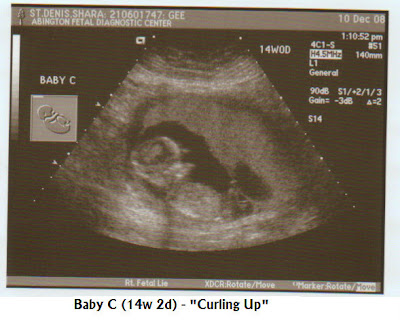

BIG day today! Today was the first ultra sounds of the SD3 in their 2nd trimester! This looked awesome! They are all moving around like crazy, in fact Baby A took forever to get a heart rate from as he wouldn't stop moving! The hearts rates are great at 167, 167 and 150 bpm. You can actually tell why as A and B were all excited, whereas Baby C was chilling more, but still managed to go from being on his back to his face during the U/S!! We were so amazed at the progress they have been making. The ultrasounds below show what we mean, but you can really see their spines and body parts, it was so cool! The doctor looked at the pictures and said everything looked great.